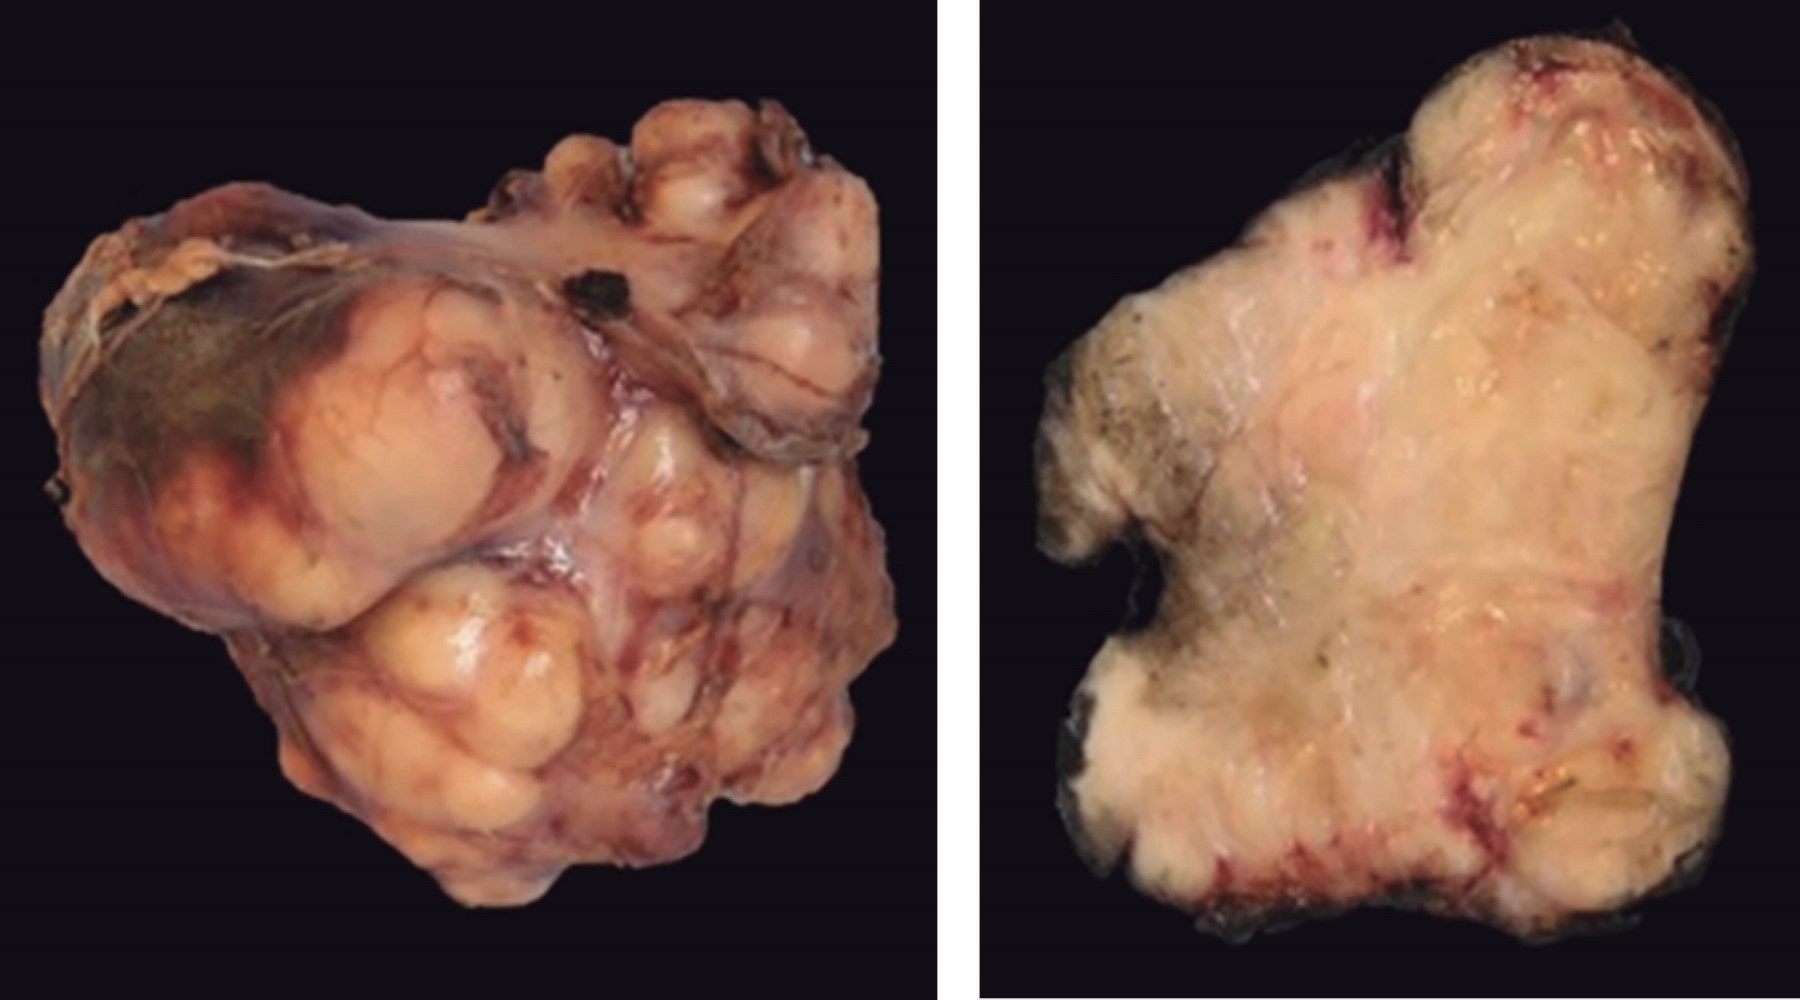

Histológicamente se reporta tejido que pesa 136 g, y en su totalidad mide 8.5 × 8 × 6 cm. Superficie lisa, multinodular, color café claro, con áreas hemorrágicas y congestivas. Al corte, de consistencia renitente, color blanquecino, de aspecto fibroso, y áreas hemorrágicas (Figura 3). Microscópicamente se observa una lesión de músculo liso difusa, con patrón de crecimiento fascicular de aspecto sarcomatoide. Las células neoplásicas son fusiformes con citoplasma fibrilar y eosinofílico. Atipia nuclear marcada, con algunos núcleos de forma alargada. La actividad mitótica es prominente y atípica. Se identifica necrosis focal y difusa. En el estudio inmunohistoquímica es positivo para actina de músculo liso, calponina y H-caldesmon en 100% del citoplasma de las células neoplásicas, con un KI-67 nuclear positivo en 40% de las células neoplásicas (Figura 4).

Figura 3